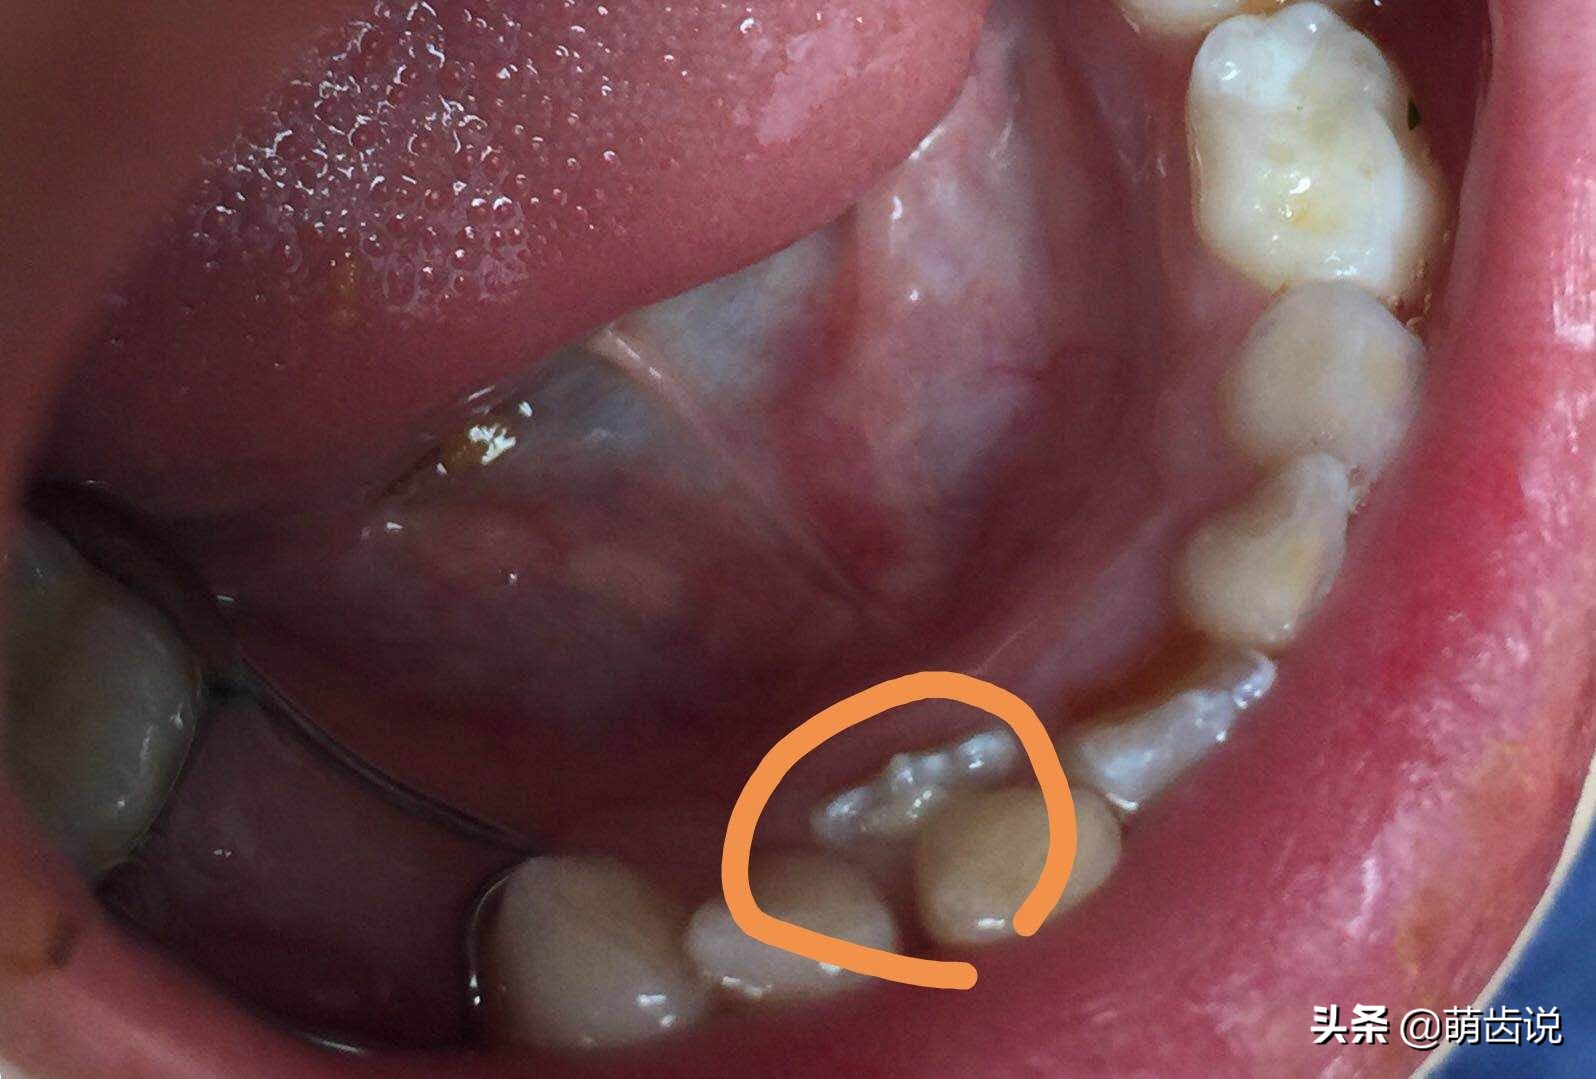

同时,长期食物嵌塞,还会增加相邻牙齿的蛀牙发病率;尤其是在儿童阶段,稍不留意,后牙的牙缝那儿就会形成大蛀洞。

食物嵌塞时,不仅会造成牙龈肿痛,还会增加相邻牙齿蛀牙的风险!